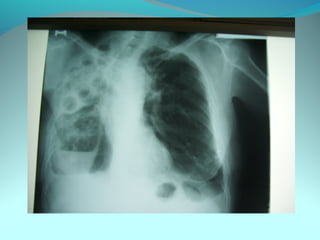

Image radiologique bilaterale

A droite : clarté sous claviculaire et axilaire droite arrondie de 3 cm de

diam entourée d une paroi de 4mm d’épaisseur

Le 1/3 sup du poumon droit est le siege d’opacité nodulaire avec

quelque clarté

A gauche: le 1/3 moyen est le siege d’opacité nodulaire et de clarté de

taille variable

DIAGNOSTIC:

Tuberculose pulmonaire bilaterale cavitaire